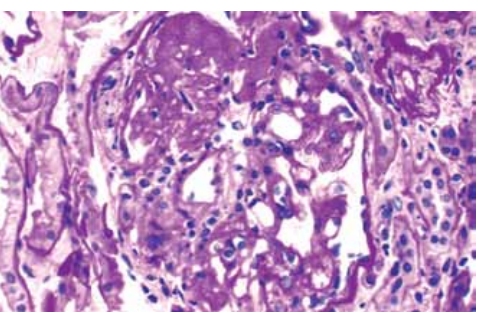

Coloração PAS

De acordo com a imagem da microscopia óptica, qual o diagnóstico do patologista?

Coloração PAS

De acordo com a imagem da microscopia óptica, qual o diagnóstico do patologista?